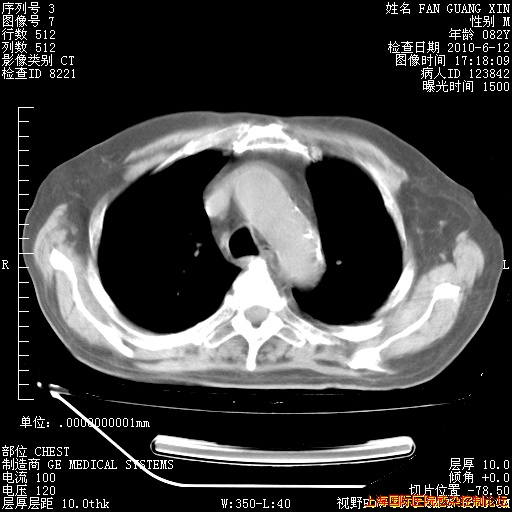

今天复查CT

今天CT

整整相隔30天的肺部CT好像有所好转啊。甲强龙减量第3天,需要观察体温。

海管,自昨日你和我通完话后,不知您岳父消化道症状有无缓解?体温怎样?阅读7.12日胸部ct,个人认为目前激素治疗是有效的,甲强龙减量是适宜的。因在抗痨治疗,需密切观察肝功、肾功能和血常规。不过,老年、长期住院和大量使用激素,很担心菌群失调发生